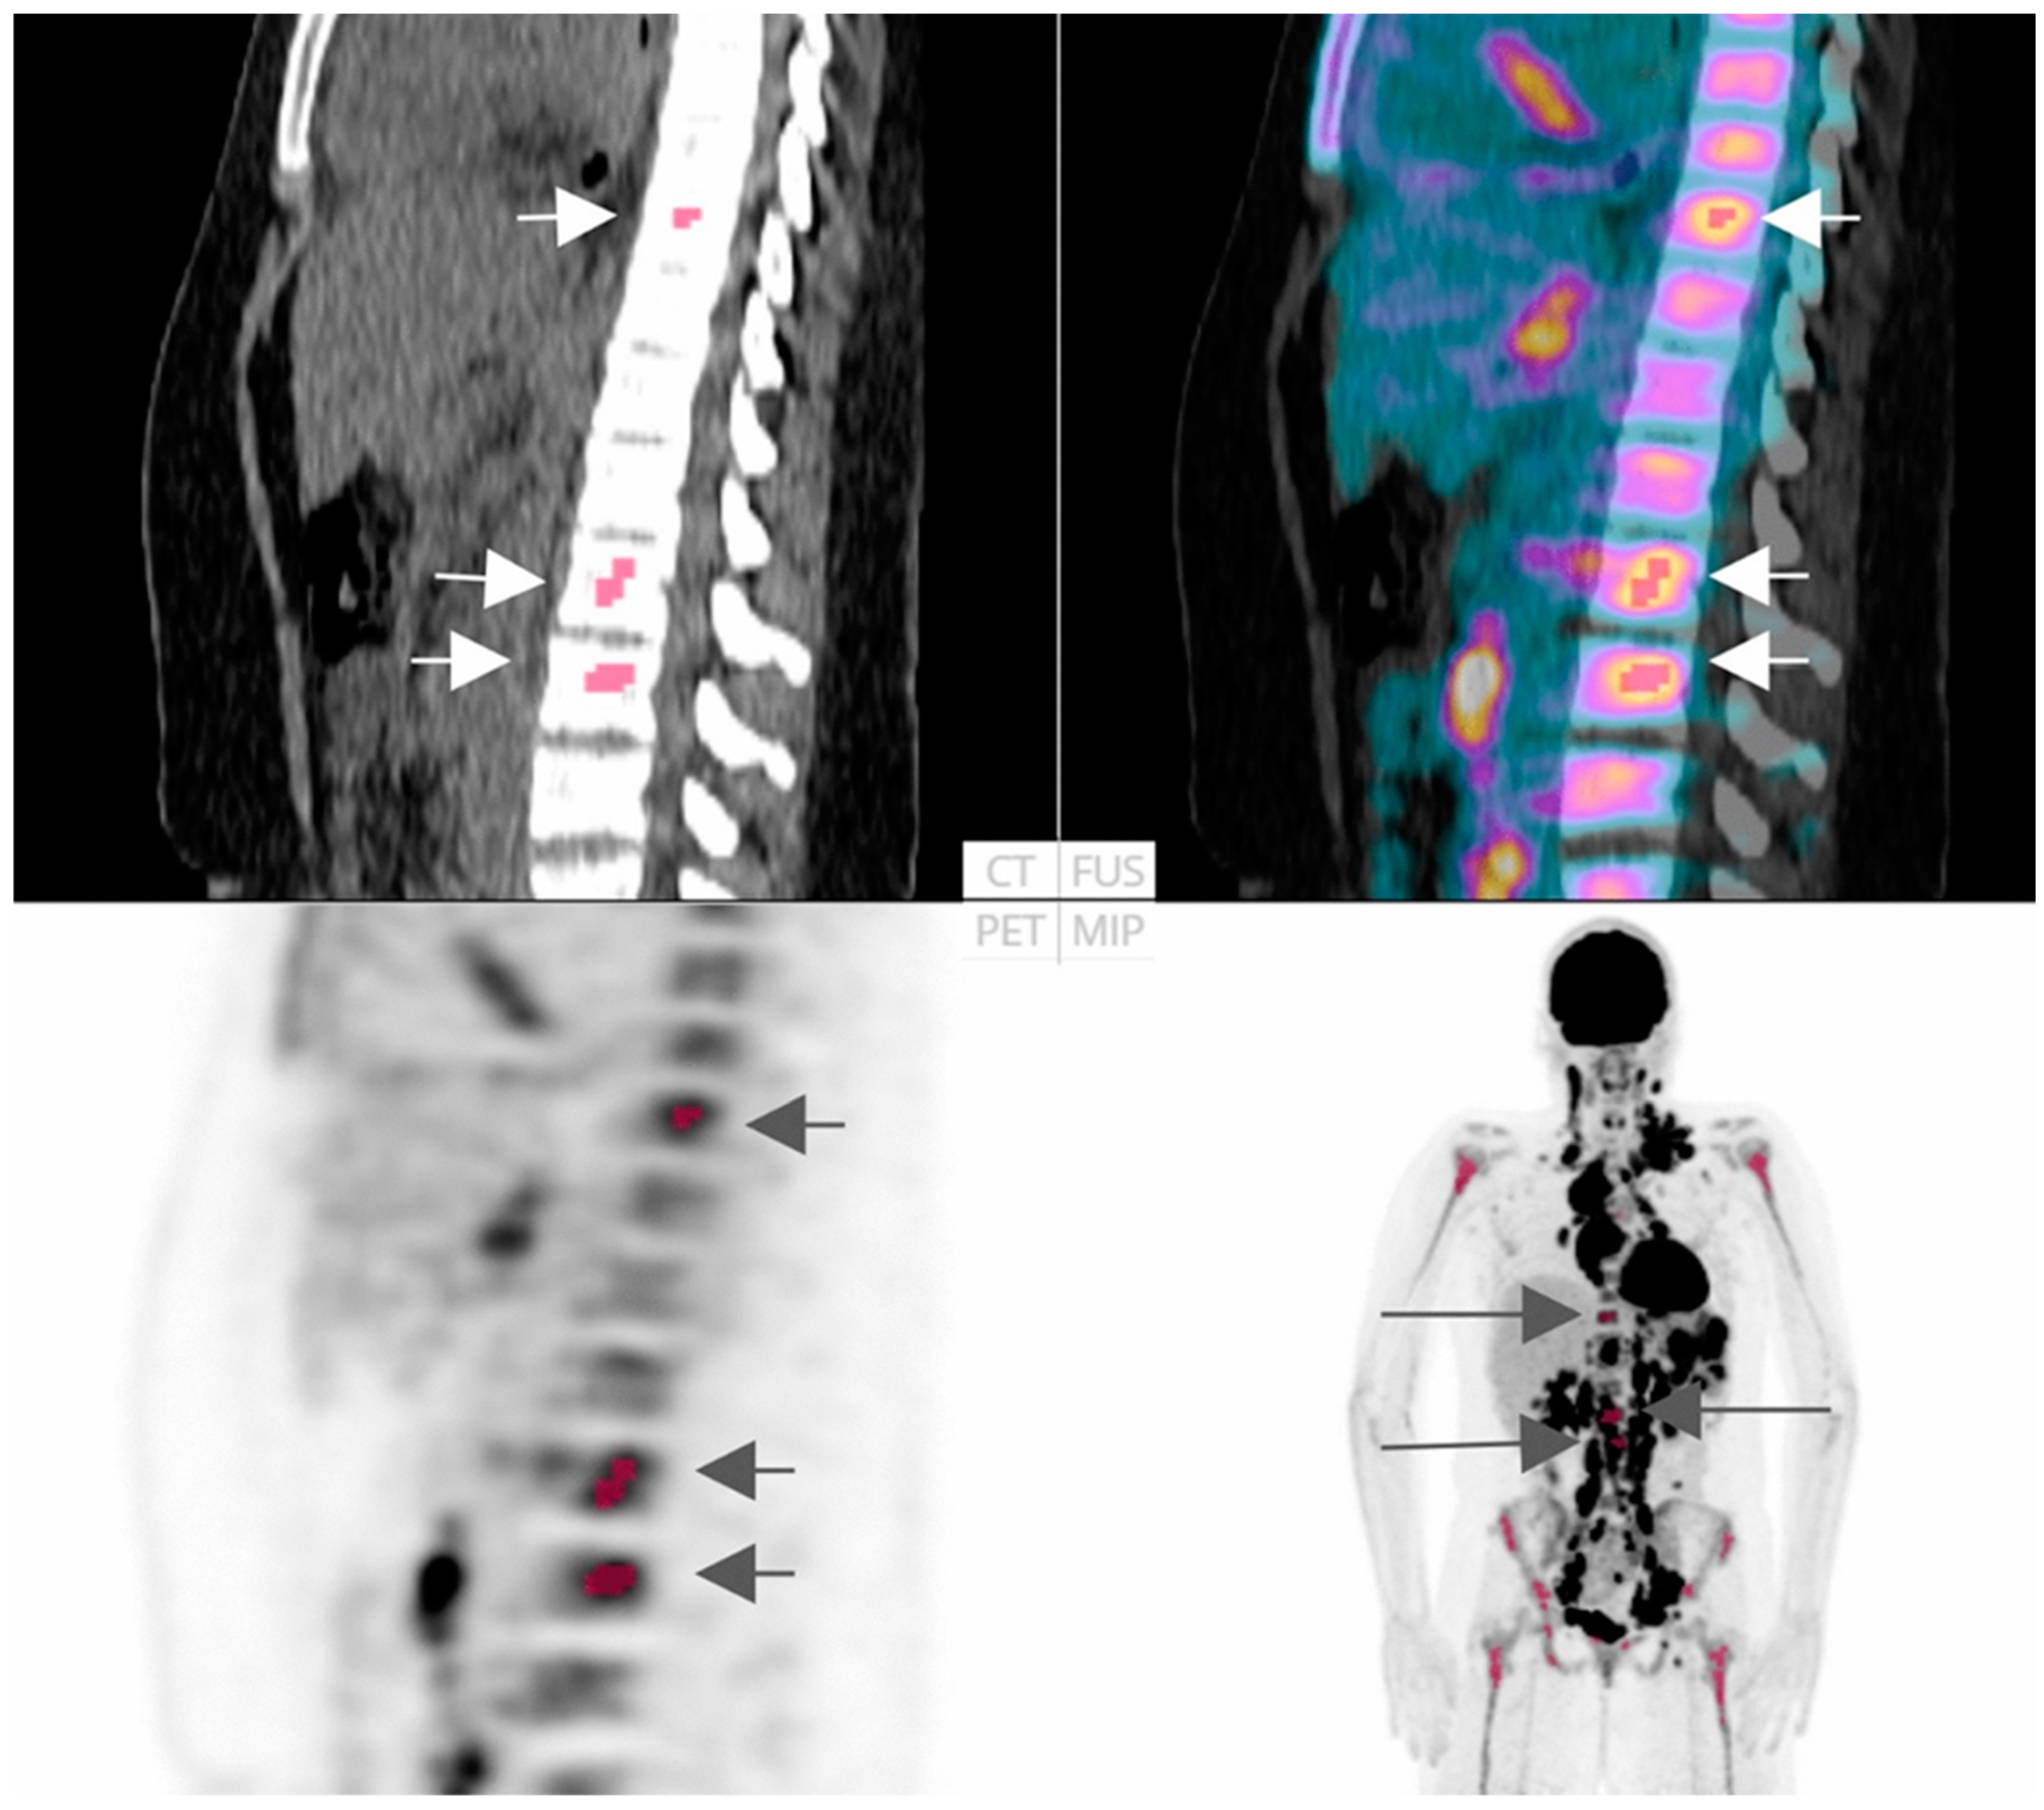

4.1.1. Diagnosis and Risk Assessment of Bone Marrow Infiltration (BMI)

| Kenawy et al. [25] | 2020 | 44 | BMI Diagnosis | Retrospective | CGITA toolbox (Math Works Inc., Natick, MA, USA, version 2015a) | Unspecified subtype | Statistical analysis | HILRE, HILZE, LRE, LZE, max spectrum, busyness, and code similarity: AUC > 0.682, p < 0.05 Univariate analysis: significant predictors of BMI were code similarity and LRE: p = 0.039, p = 0.02 respectively. Multivariate analysis: significant predictor of BMI was LRE: p = 0.031 | BMI diagnosis is improved by the combination of 18F-FDG PET/CT radiomic features (particularly LRE) and visual evaluation. |